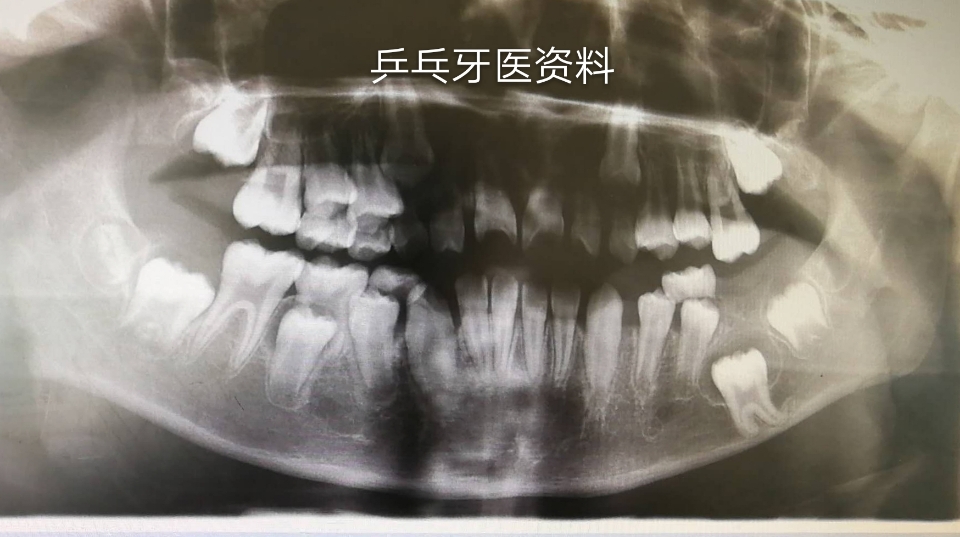

口腔检查:左下六龄牙(36)未萌出,其它3个六龄牙均正常萌出建合。

放射检查见片: 处理:局麻下拔除36